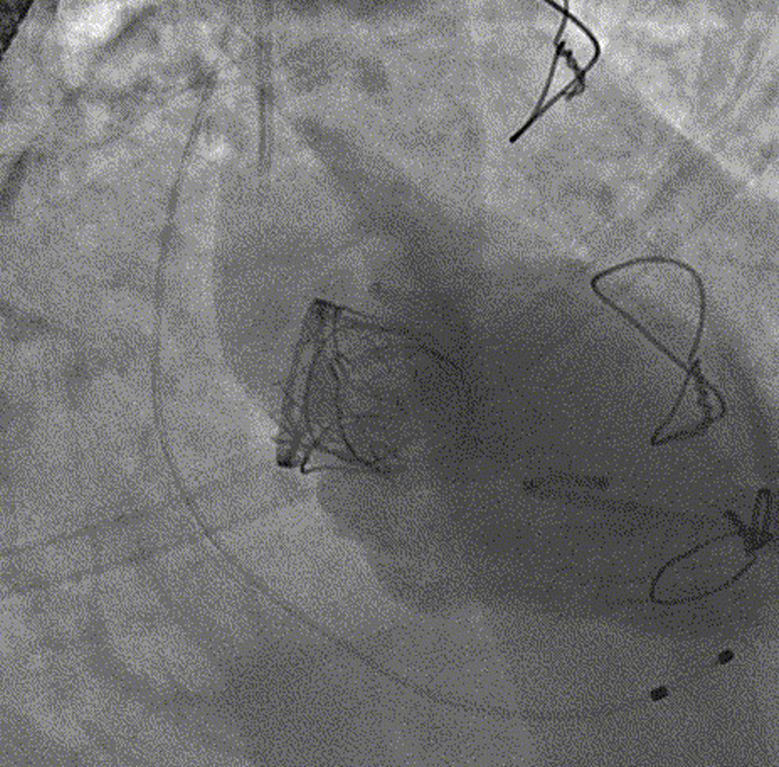

心外科瓣膜中心张海波教授团队创新性使用J Valve系统经过术中技术改进,在2019年1月国际上首次成功完成经心尖途径二尖瓣毁损生物瓣的微创J Valve瓣中瓣技术。目前该手术技术达到了国际先进水平。手术完全在心脏跳动下进行,不用传统的开胸游离粘连和体外循环,仅仅心尖穿刺途径完成整个介入瓣膜的植入,整个手术核心环节仅仅十分钟。在目前成功完成的平均年龄76岁,所有患者恢复顺利,没有明显并发症,受到众多老年生物瓣术后患者的热烈欢迎。

国产百仁介入瓣膜完成的二尖瓣生物瓣毁损的介入瓣中瓣技术

在此基础上,安贞医院心外科瓣膜中心(九病区)团队继续深入研究技术创新,又在2019年国际上首次成功完成了更加复杂的一个穿刺点进行双瓣膜置换(二尖瓣生物瓣毁损、主动脉瓣疾病或者主动脉瓣生物瓣毁损)的经导管J Valve微创手术,也均获得了成功。该技术仅仅利用心尖的同一穿刺点,在心脏跳动下,不用开胸体外循环,先后进行二尖瓣生物瓣瓣中瓣技术和主动脉瓣的TAVI手术,核心手术时间也就二十分钟。2021年在纪智礼书记、张宏家院长、周玉杰副院长大力支持下,又率先进行国产佰仁介入瓣膜的瓣中瓣技术研究获得巨大成功。

中国微创心外科大会直播生物瓣毁损的微创介入瓣中瓣手术

日前2021年中国微创心外科大会邀请张海波教授团队转播2台二尖瓣毁损的瓣中瓣手术。两例患者均为高龄,二尖瓣生物瓣置换术后十余年,瓣膜毁损后出现心衰、浮肿、胸腔积液等临床症状,反复救治多家医院因为年龄较大多脏器功能不全而认为再次开胸体外循环换瓣手术风险大,此次均为慕名前来安贞医院心外科瓣膜中心救治。2台手术分别采用国产J Valve瓣膜和国产百仁瓣膜,手术均获得顺利成功,国内有能力同时完成不同介入瓣膜的瓣中瓣技术仅有两三家大型中心。核心操作时间仅仅几分钟的时间,整个流程行云流水,术后造影和三维超声显示介入瓣膜功能良好,术前的瓣膜毁损的大量反流和重度狭窄消失,左房压力和肺动脉压即刻明显下降,手术效果立竿见影非常成功,获得了与会网络嘉宾专家的称赞。